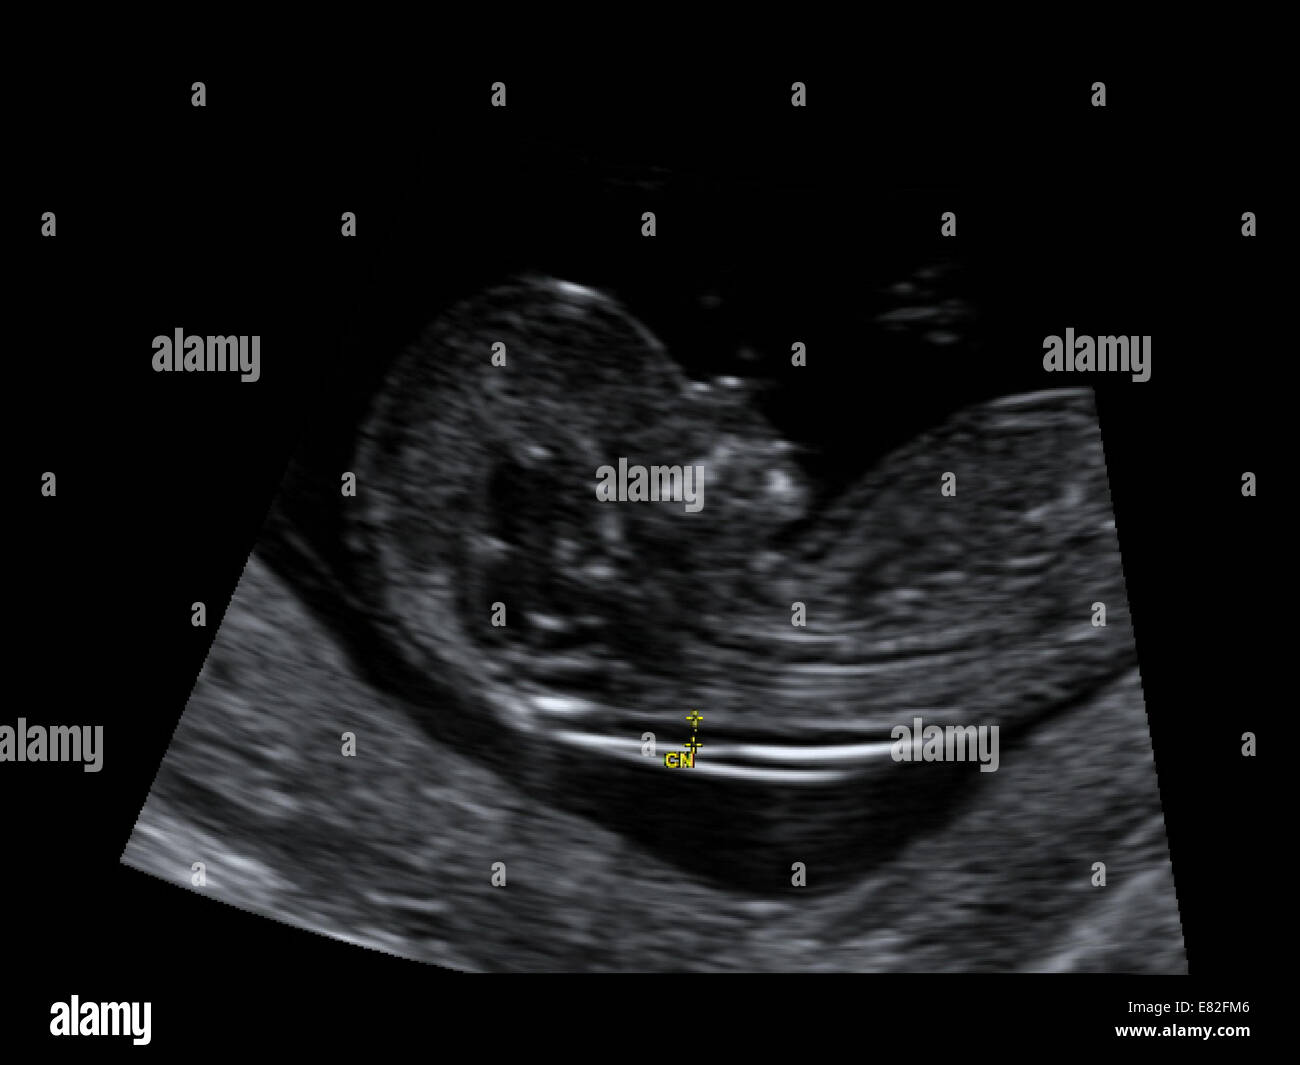

Auf einem Ultraschall ein Bild eines sich entwickelnden Fötus auch Sonogramm genannt können sichtbare Anzeichen dafür vorliegen dass ein Baby das Down-Syndrom hat. Down-Syndrom während der Schwangerschaft betrifft Jungen und Mädchen gleichermaßen. Für 1100 gesunde Babys wird ein Baby mit diesem Syndrom geboren.

Ultraschallbild Eines Fotus Zeigt Nackentransparenz Scan Fur Down Syndrom Gestational Alter 12 Wochen Und 3 Tage Stockfotografie Alamy

Anzeichen down syndrom fötus. Schwangerschaftswoche per Ultraschall die Dicke der Hautfalte im Nacken des Kindes und kann damit zwischen 75 und 80 Prozent aller Föten mit Down-Syndrom erkennen weil bei diesen die Nackenfalte dicker ist. März ist ein Tag der Solidarität mit Menschen die Down-Syndrom haben. Die Ursachen sind genetisch bedingt dennoch handelt es sich beim Down-Syndrom nicht um eine Erbkrankheit.

Diese Untersuchungsmethode misst zwischen der 10. Dritte Fontanelle auf der Naht zwischen großer und kleiner Fontanelle zusätzliche Hautfalte im Genick.